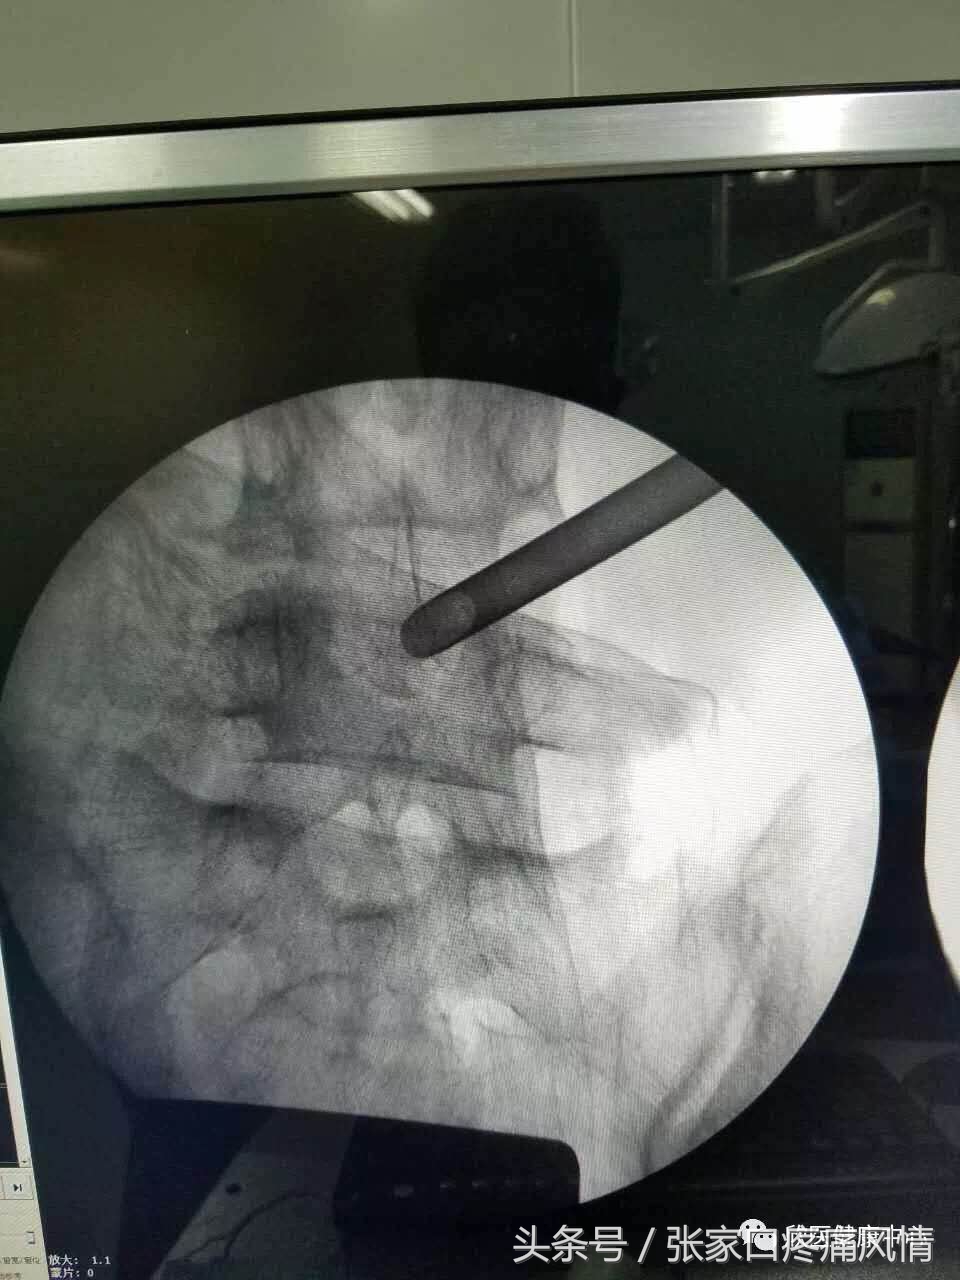

射频热凝机理是通过磁场发射出高频率射频电流,射频电流在工作电极尖端产生变化磁场,使磁场覆盖的靶点组织内分子运动摩擦生热,热凝毁损靶点区域组织。射频热凝靶点治疗是在C型X光机下准确定位,数字减影下时时监测,直接把突出部位的间盘髓核变性、凝固;收缩减小体积,解除压迫。不伤及正常的髓核组织,同时修补了纤维环的破裂、灭活了盘内新生病变超敏的神经未梢,直接阻断了髓核液中糖蛋白和β蛋白的释放,温热效应对损伤的纤维环、水肿的神经根、椎管内的炎性反应起到良好的治疗作用,治疗后症状症状立即消失或减轻。是目前国际上公认的安全见效快、病人痛苦小、风险低的微创治疗方法之一。

射频消融术

经皮穿刺激光椎间盘减压术(percutaneous laser disk decompression,PLDD),是指在C形臂X线或CT的引导下,用16G/18G穿刺针刺人病变颈/腰椎间盘,通过穿刺针导人直径为200~800 m光纤。然后启动半导体激光治疗系统发射激光,将椎间盘汽化,从而使其局部消融、降低椎间盘内压力,达到对硬膜囊和神经根减压的目的。PLDD适应证包括纤维环完整的包含型椎间盘突出伴与椎间盘病变节段相符的根性症状,对非包含型或游离型椎间盘突出、腰椎管狭窄、侧隐窝狭窄等则不宜行PLDD。